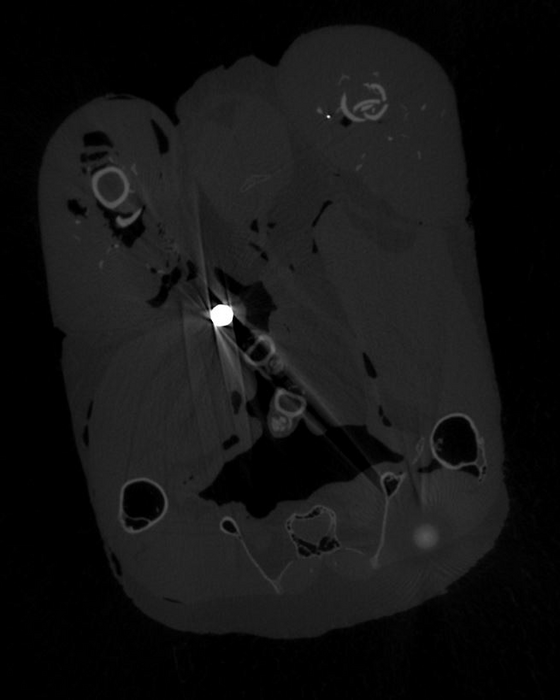

The researchers used a high-resolution CT (computerised tomography) scanner to locate the lead fragments in the pheasant meat in three dimensions, and measure their size and weight. The meat was then dissolved, allowing the larger fragments to be extracted and analysed further to confirm they were lead.

An average of 3.5 lead pellets and 39 lead fragments of less than 1mm wide were detected per pheasant. The smallest fragments were 0.07mm wide – at the limit of resolution for the CT scanner for specimens of this size - and the researchers say it is likely that even smaller fragments were also present.

The lead pieces were widely distributed within the birds’ tissues and some of the small fragments were over 50mm from the nearest lead shot pellet.